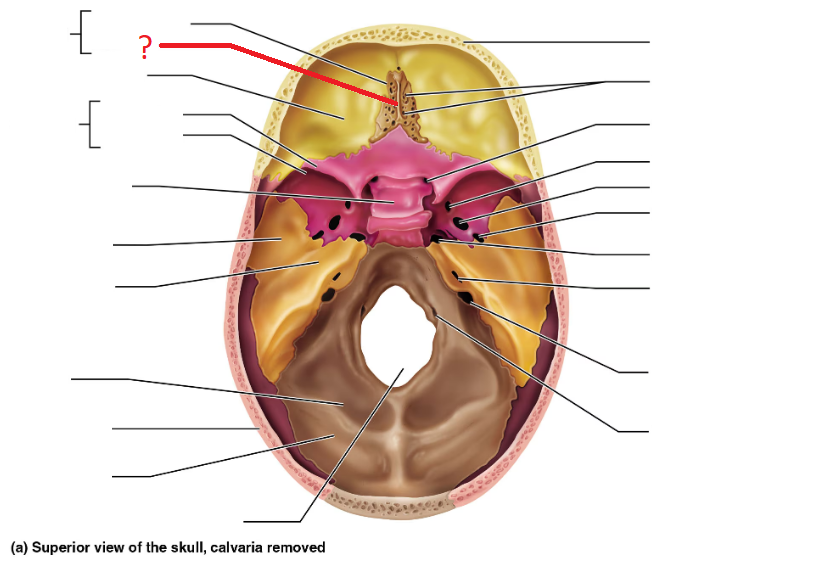

Ethmoid bone

Crista galli

Cribriform plate

Greater sphenoid wing

Lesser sphenoid wing

Sella turcica, protects pituitary gland

Foramen magnum (superior interior view)